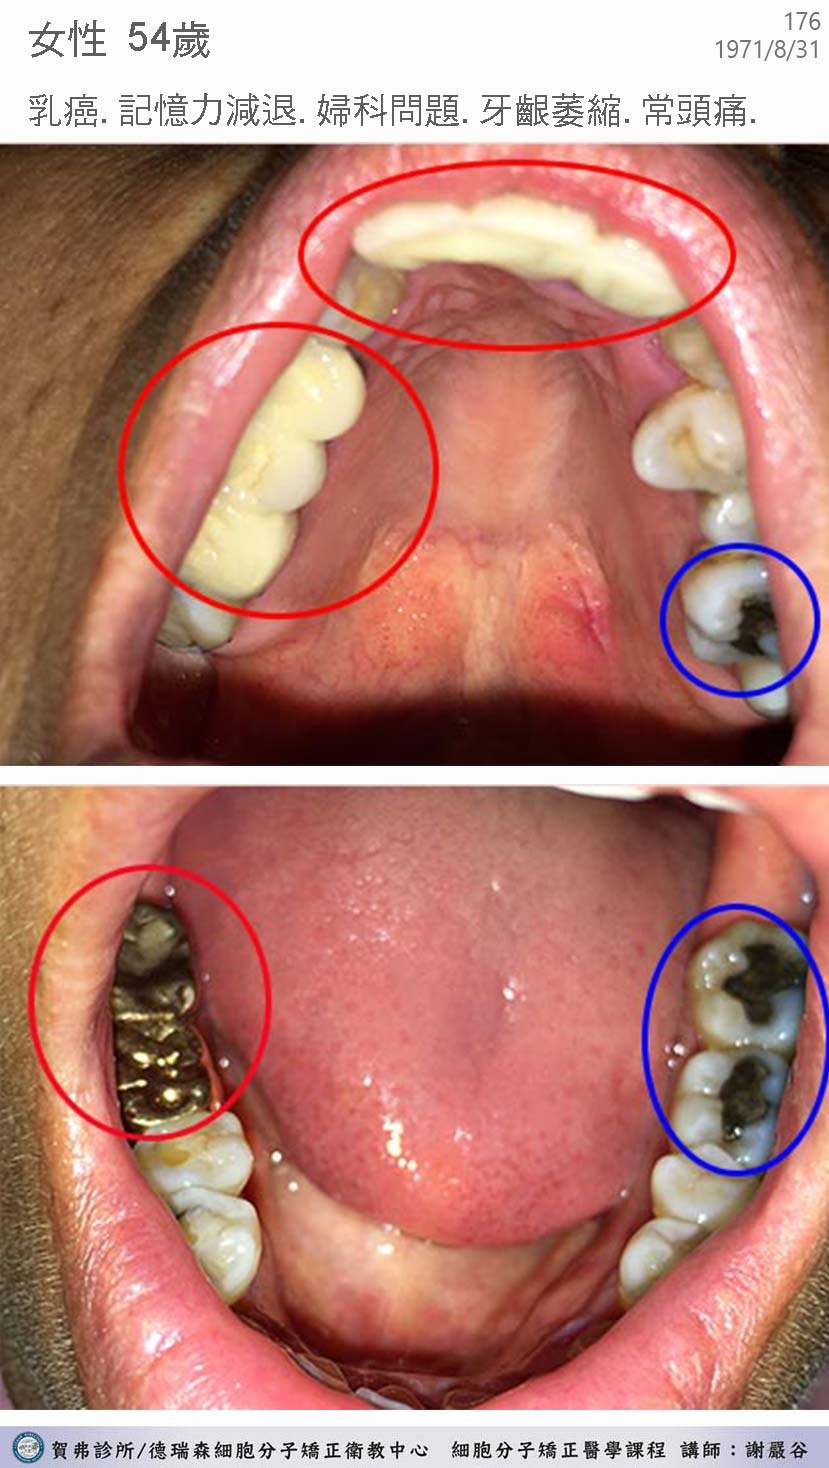

典型汞中毒症候群個案 hgscs0001